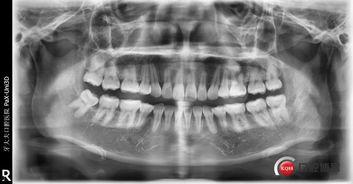

那么,土法拔牙究竟是怎样的呢?简单来说,就是利用一些简单的工具,如钳子、镊子等,将牙齿从牙龈中拔出。听起来是不是有点惊心动魄?别急,接下来我会为你详细揭秘。

在土法拔牙视频中,我们最常见的工具就是钳子和镊子。这些工具看似简单,却蕴含着丰富的技巧。比如,钳子要选择合适的型号,以免损伤牙龈;镊子则要灵活运用,确保牙齿顺利拔出。

(2)定位:确定牙齿的位置,以便准确拔出。

(3)夹住牙齿:使用钳子或镊子夹住牙齿,注意力度要适中。

(4)拔出牙齿:在拔牙过程中,要不断调整力度和角度,确保牙齿顺利拔出。